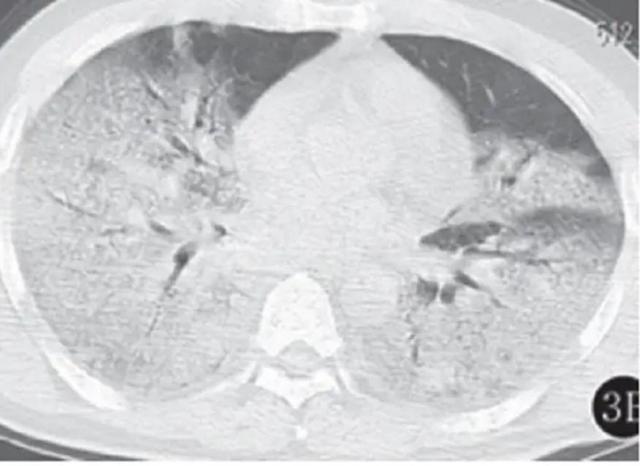

解放军总医院第五医学中心(302医院)王福生院士团队,近期于《柳叶刀·呼吸医学》期刊上发表了首份新冠肺炎逝者病理报告,这项病理分析不是来自完整的尸检,而是通过对一位新冠肺炎逝者进行微创病理检查获得的。团队人员对患者的肺、肝和心脏进行了组织样本检测。

其中,肺部组织学检测显示,患者肺部表现为弥漫性肺泡损伤和肺透明膜形成,肺部总体病理特征与SARS、中东呼吸综合征(MERS)相似。

(图片来源:腾讯看点视频截图)